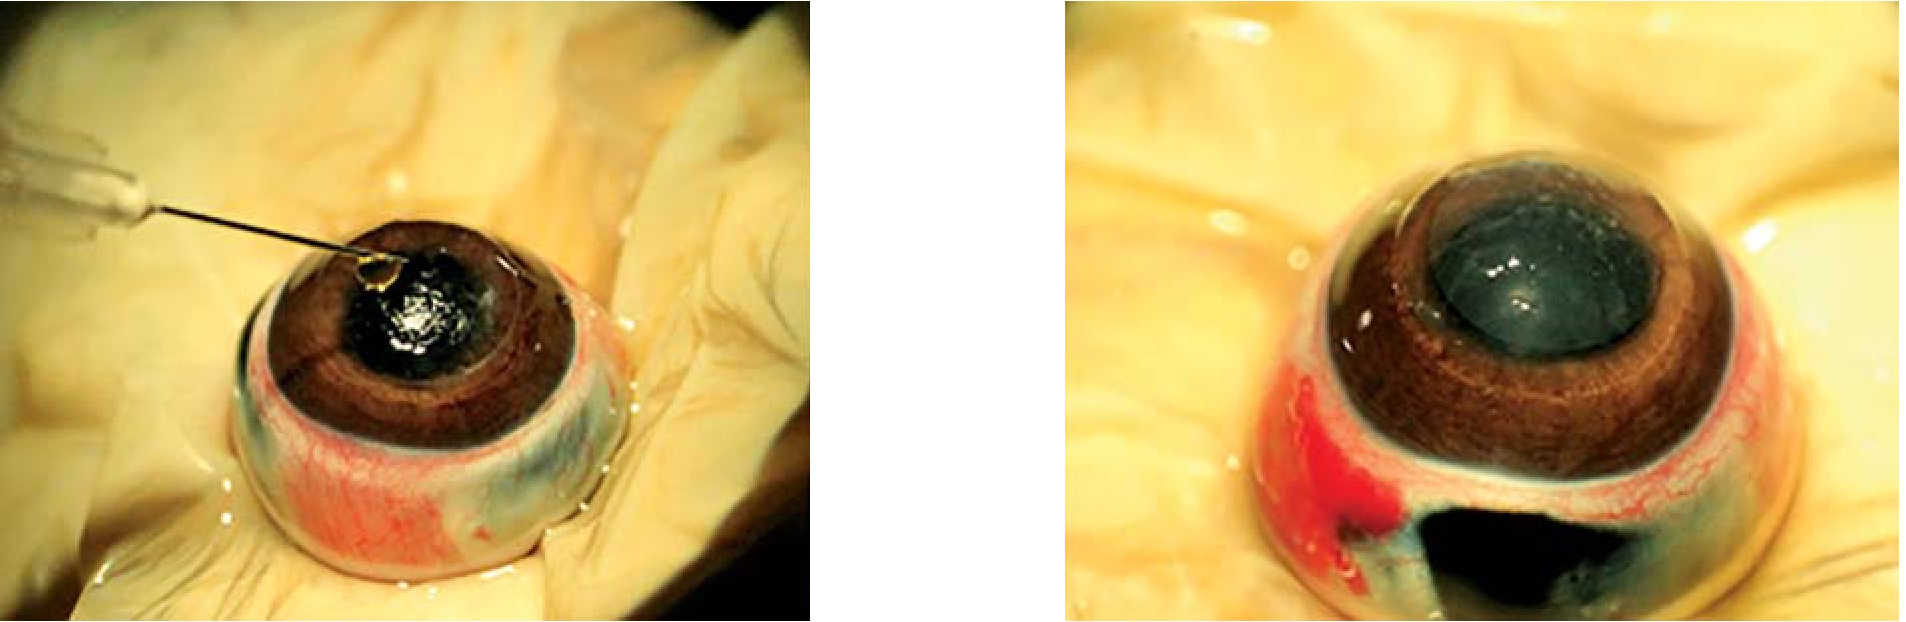

Апробация клея проведена на глазах трех кроликов (6 глазах) породы шиншилла посредством вклейки амниотической мембраны (АМ) после поверхностной кератэктомии (рис. 1). Заранее проводилась заготовка компонентов ФК. Трепаном на дозированную глубину в 100–150 мкм выполнялась поверхностная кератэктомия. На строму роговицы наносилась половина объемов компонентов, смешанных в одном шприце. Сразу после этого выкраивалась АМ необходимого диаметра и накладывалась на строму роговицы. Проводилась экспозиция в течение 1 мин. Далее на роговичную поверхность наносились смешанные в одном шприце остаточные объемы компонентов полученного двухкомпонентного ФК.

Рис. 1. Процесс приклеивания АМ на строму роговицы после частичной поверхностной кератэктомии